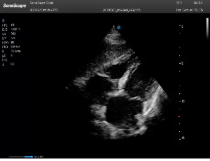

不同的探頭對應(yīng)于不同的臨床領(lǐng)域,不同的探頭頻率也應(yīng)用于不同的人體組織。超聲波在人體中的衰減與探頭頻率有關(guān),探頭頻率越高,穿透力越弱,分辨率越高,而探頭頻率越低,穿透力越強,分辨率越低。因此在檢查淺表器官時應(yīng)選用高頻探頭,而檢查深部臟器時則選用穿透性強的低頻探頭。

(2)握持式:常用于劍突下切面的獲取。